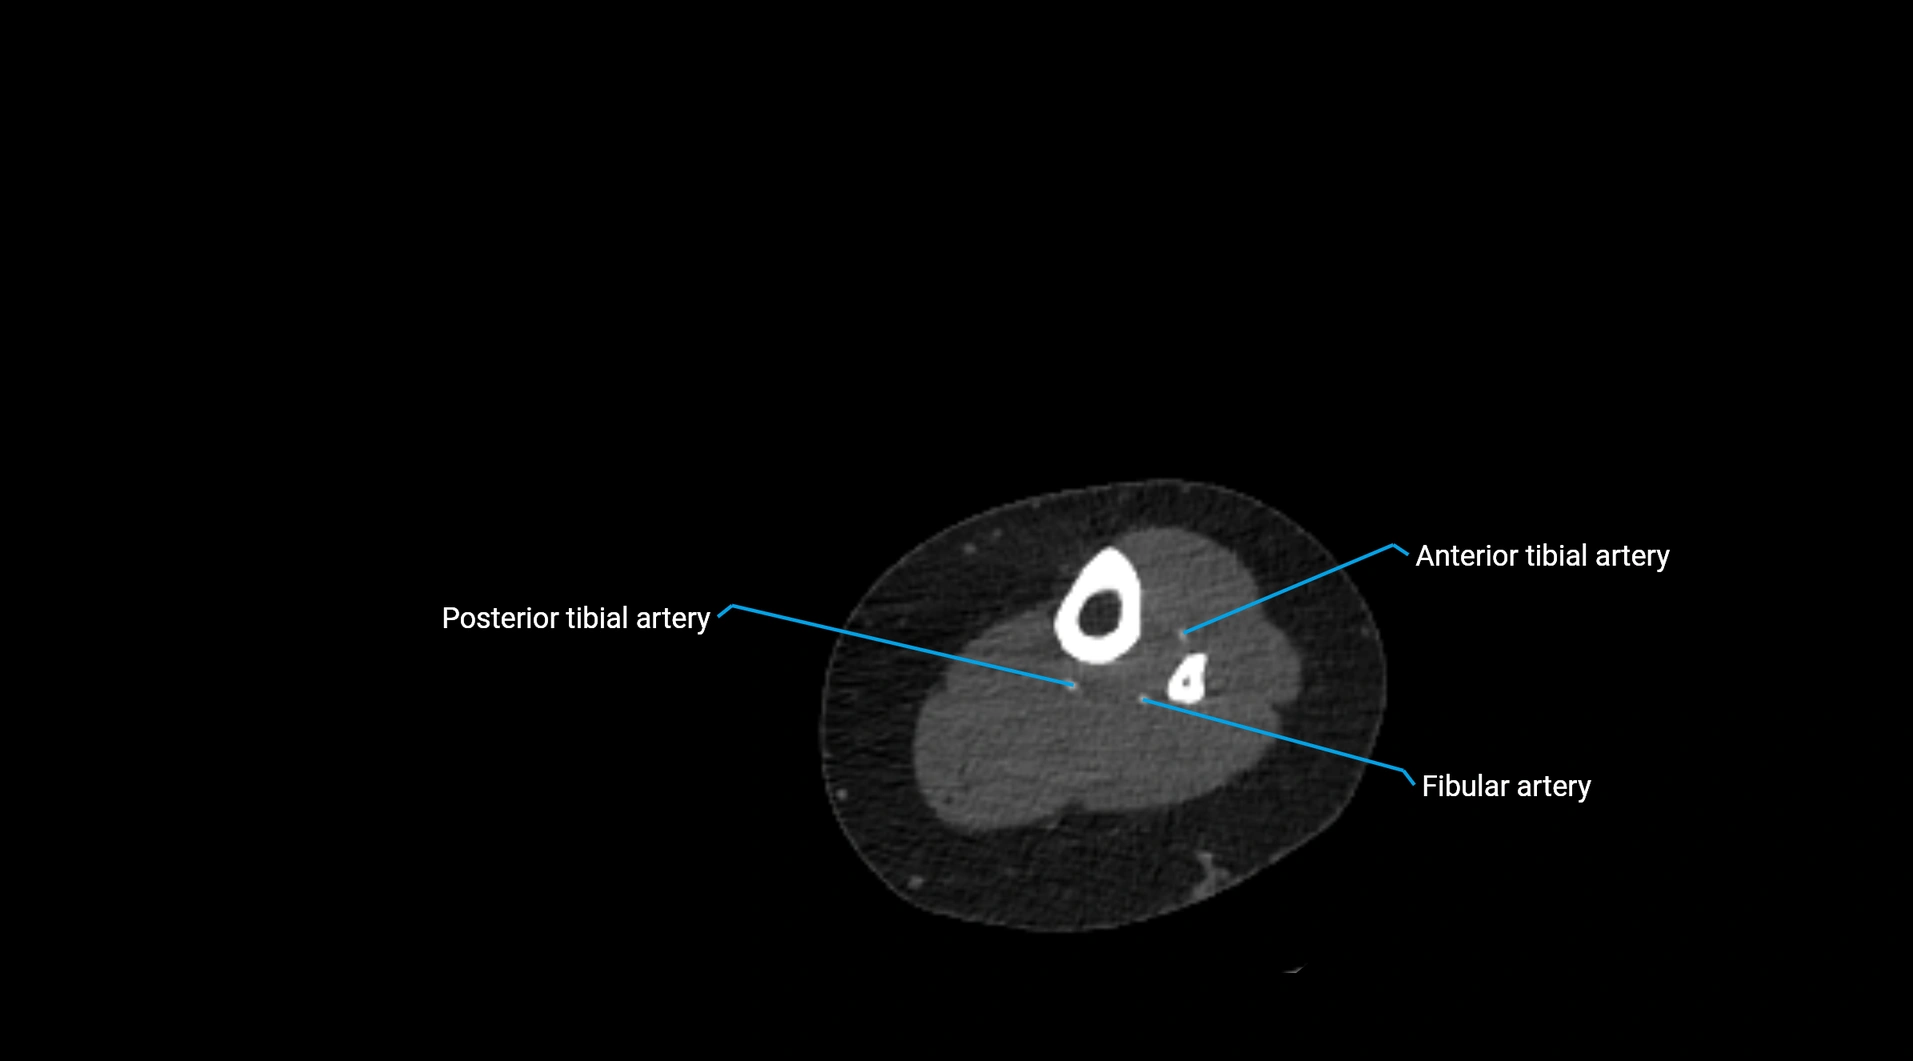

CT images

image

Contrast-enhanced CT (CTA):

• Gold standard for abdominal aortic imaging

• Provides excellent detail of lumen, wall, aneurysm, thrombus, and branch vessels

• Multiplanar and 3D reconstructions help in aneurysm measurement, stent graft planning, and dissection evaluation